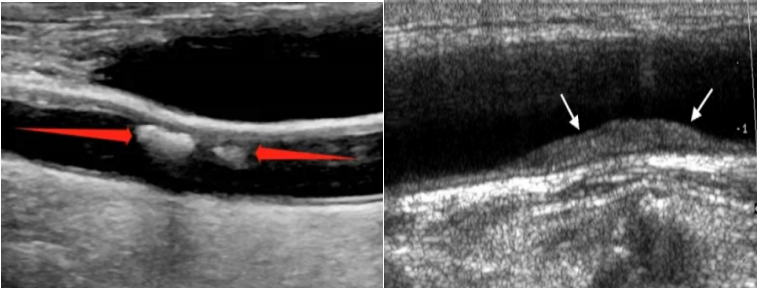

頸動(dòng)脈超聲是診斷評估動(dòng)脈壁病變的有效手段之一,利用超聲波技術(shù),觀察血管走行、內(nèi)-中膜是否增厚、有無斑塊形成、斑塊的回聲性質(zhì)、是否有血管狹窄及狹窄程度、有無閉塞等詳細(xì)情況,并對病變進(jìn)行測量和定位,同時(shí)對動(dòng)脈的血流動(dòng)力學(xué)結(jié)果進(jìn)行分析。所謂“頸動(dòng)脈超聲”說的是頸動(dòng)脈系統(tǒng),根據(jù)部位不同可分為頸總動(dòng)脈、頸內(nèi)動(dòng)脈、頸外動(dòng)脈,通常我們還會同時(shí)檢查雙側(cè)椎動(dòng)脈及鎖骨下動(dòng)脈。

頸動(dòng)脈斑塊是頸動(dòng)脈最常見的動(dòng)脈病變,通俗來說,頸動(dòng)脈斑塊就像水管里的水銹。受各種因素的影響,人體動(dòng)脈血管會逐漸老化、硬化,血管內(nèi)的“雜質(zhì)”隨著血流的流動(dòng)不斷地沉積到血管壁上,在血管壁上形成增厚的凸起,這就是斑塊形成的過程。全身的動(dòng)脈血管都可能“長斑”,其中尤以頸動(dòng)脈斑塊危害最大!